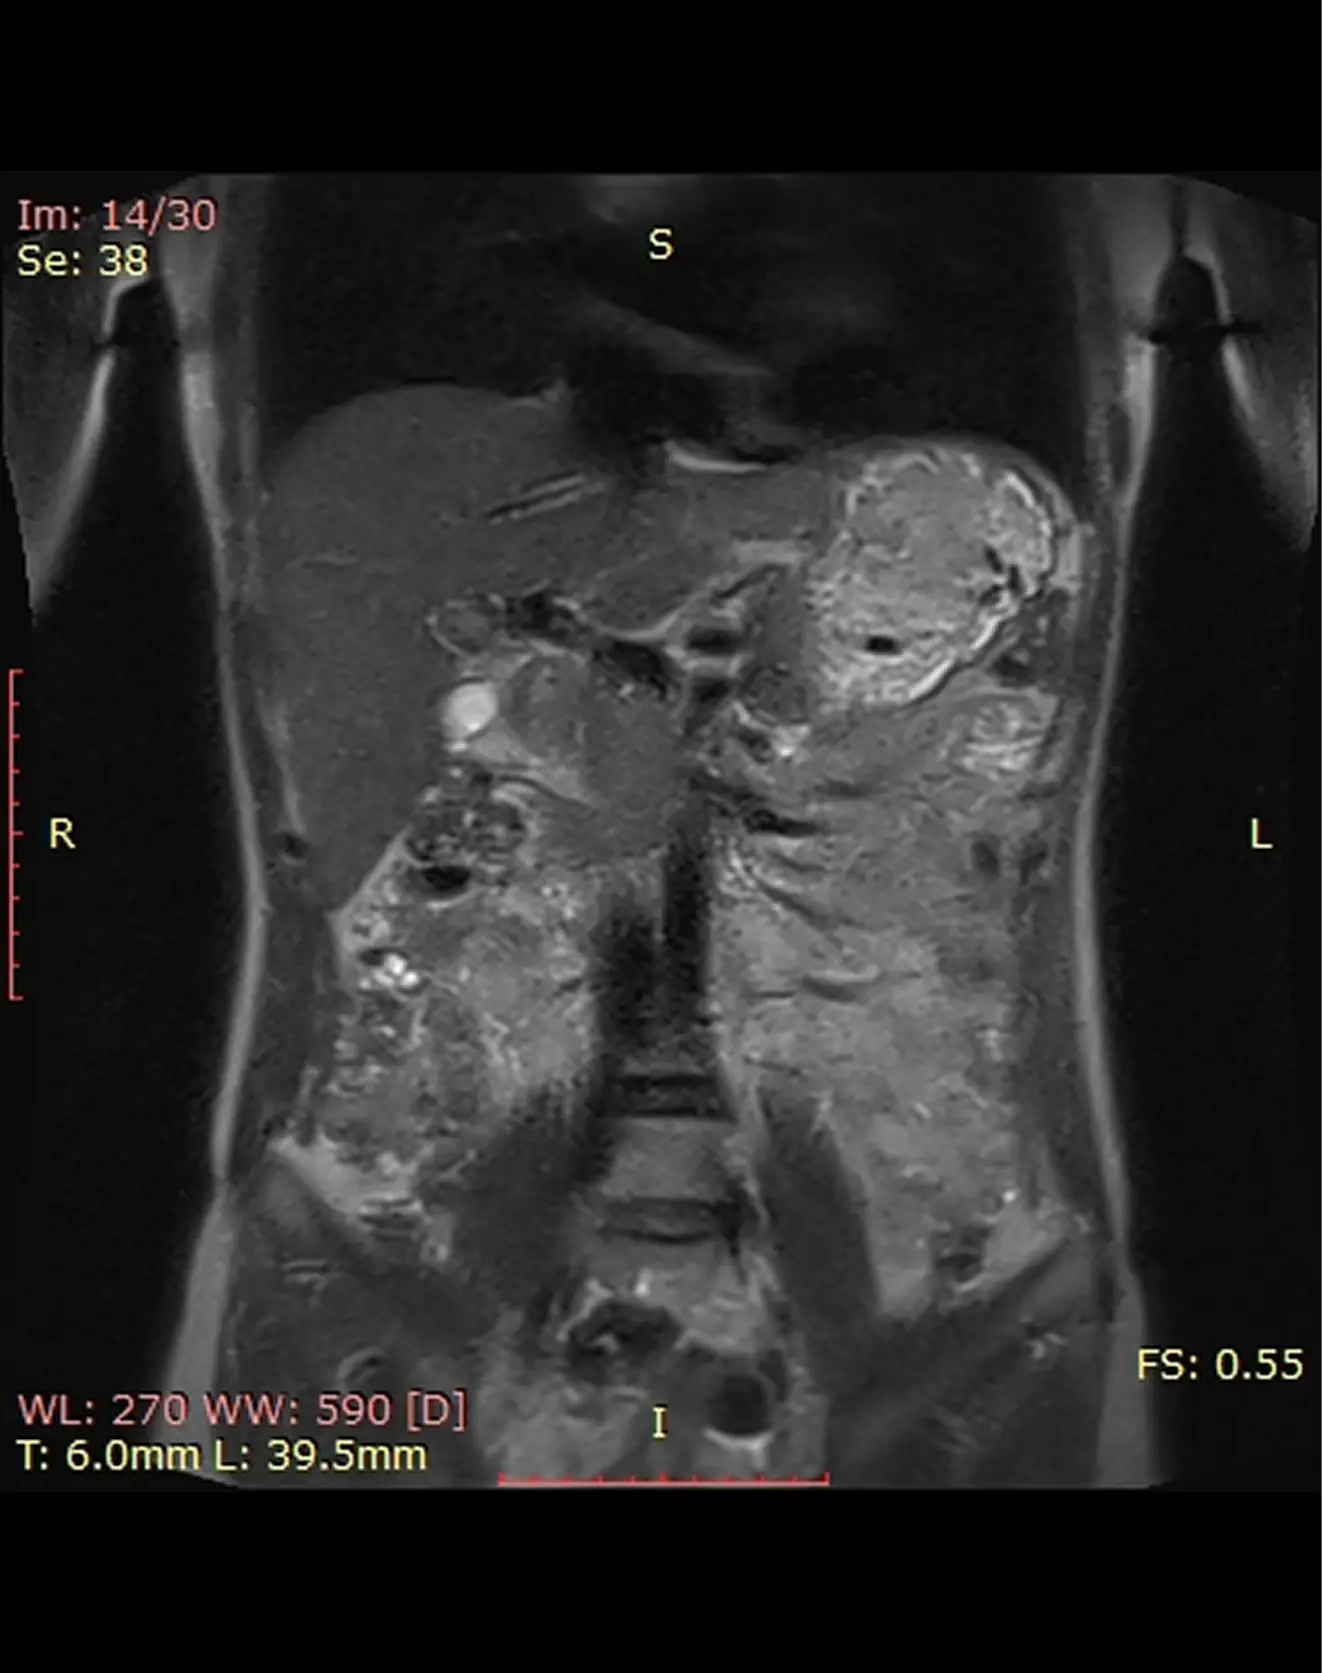

Подготовка к МРТ органов брюшной полости и желчных протоков (МРХПГ)